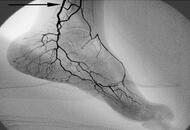

日常小动作帮助脚部保健

我们经常说脚连接着身体的其他器官及穴位,当脚部出现一些症状或者说变化时,便能判别出身体哪些地方出现了健康问题。中医对于这些信号有哪些应对方法呢,一起来了解下吧。